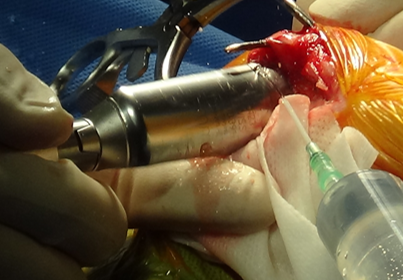

3) 수술 과정

수술 부위를 절개한 뒤, 정강이뼈 위쪽을 안전하게 노출한뒤 TPLO 전용 톱을 이용해 정강이뼈 위쪽을 원형으로 절골합니다.

.png)

수술 전 계획에서 계산한 값대로, 절골된 뼈 조각을 필요한 만큼 회전시켜 관절면 경사를 조정합니다.